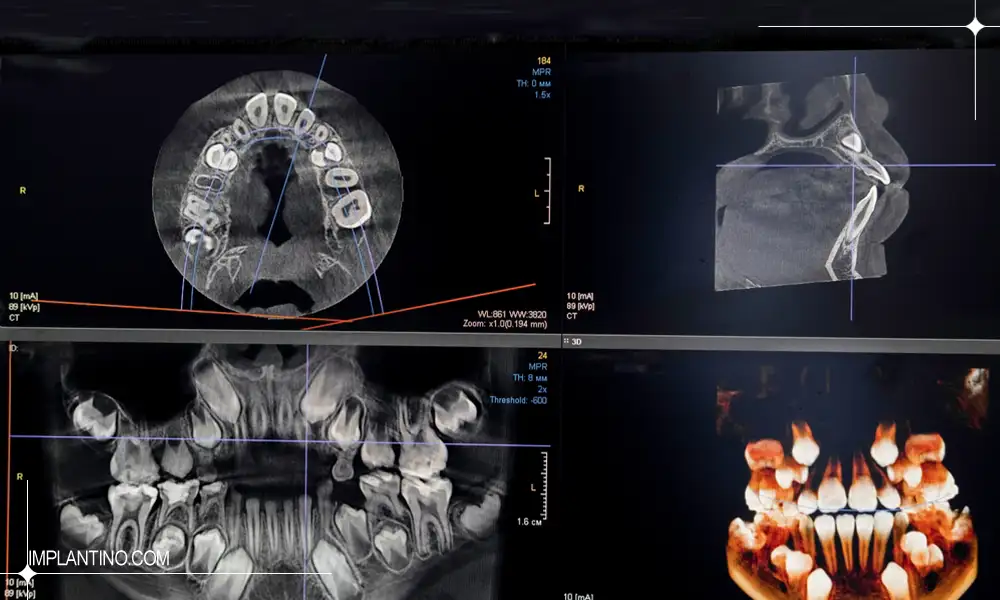

عکس CBCT یا Cone Beam Computed Tomography نوعی تصویربرداری پیشرفته است که با استفاده از اشعه ایکس و تکنولوژی پرتو مخروطی، تصاویر سه بعدی از دهان، دندان ها، استخوان فک و حتی سینوس ها ارائه می دهد. این نوع عکس به دندانپزشک این امکان را می دهد که جزئیات ریز ساختاری را که در عکس های معمولی قابل مشاهده نیستند، به طور دقیق بررسی کند.

برخلاف رادیوگرافی های دوبعدی مثل عکس پانورامیک (OPG)، عکس CBCT اطلاعات سه بعدی فراهم می کند و همین موضوع باعث شده در تشخیص و برنامه ریزی درمان های پیچیده، مانند ایمپلنت دندان، جراحی های فک و بررسی ضایعات استخوانی، ارزش بسیار بالایی داشته باشد.

تفسیر عکس CBCT دندان فرایندی تخصصی است که علاوه بر مشاهده سطحی دندان ها، به بررسی دقیق ساختارهای استخوانی، کانال های عصبی، سینوس ها و بافت های اطراف دندان می پردازد. برخلاف تصاویر دوبعدی، CBCT امکان تحلیل سه بعدی با دقت میلی متری را فراهم می کند، که در برنامه ریزی درمان های پیچیده از جمله ایمپلنت، جراحی فک و درمان های اندودنتیک ضروری است.